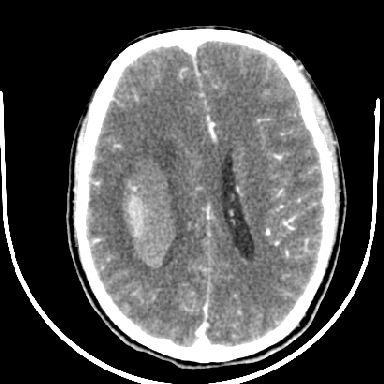

但脑出血早期做增强是不是有点太冒险了?

术中抽出40ml陈旧血液,血肿底部似见一条索血管影